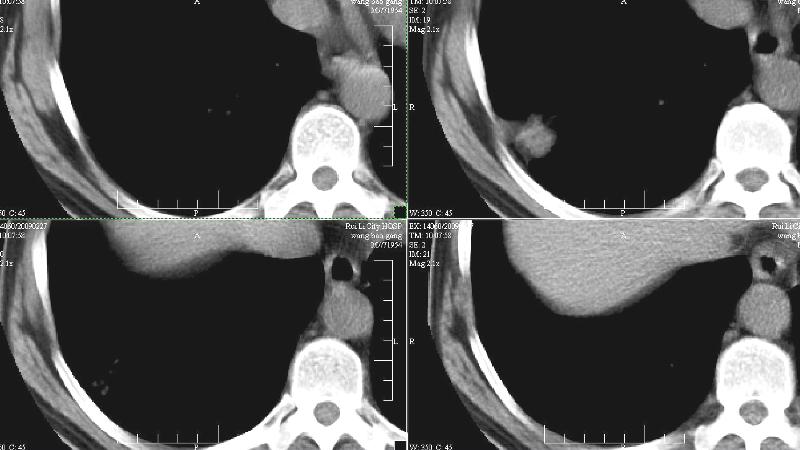

bp:180/120.神清,心肺未见阳性征象。临床高度怀疑肺癌(脑转移)。胸片:右下肺外基底段3.0x3.0cm球形病灶,考虑周围性肺癌。ct:右肺下叶外侧基底段病灶,考虑炎性结节可能性大,其它?建议治疗后复查。